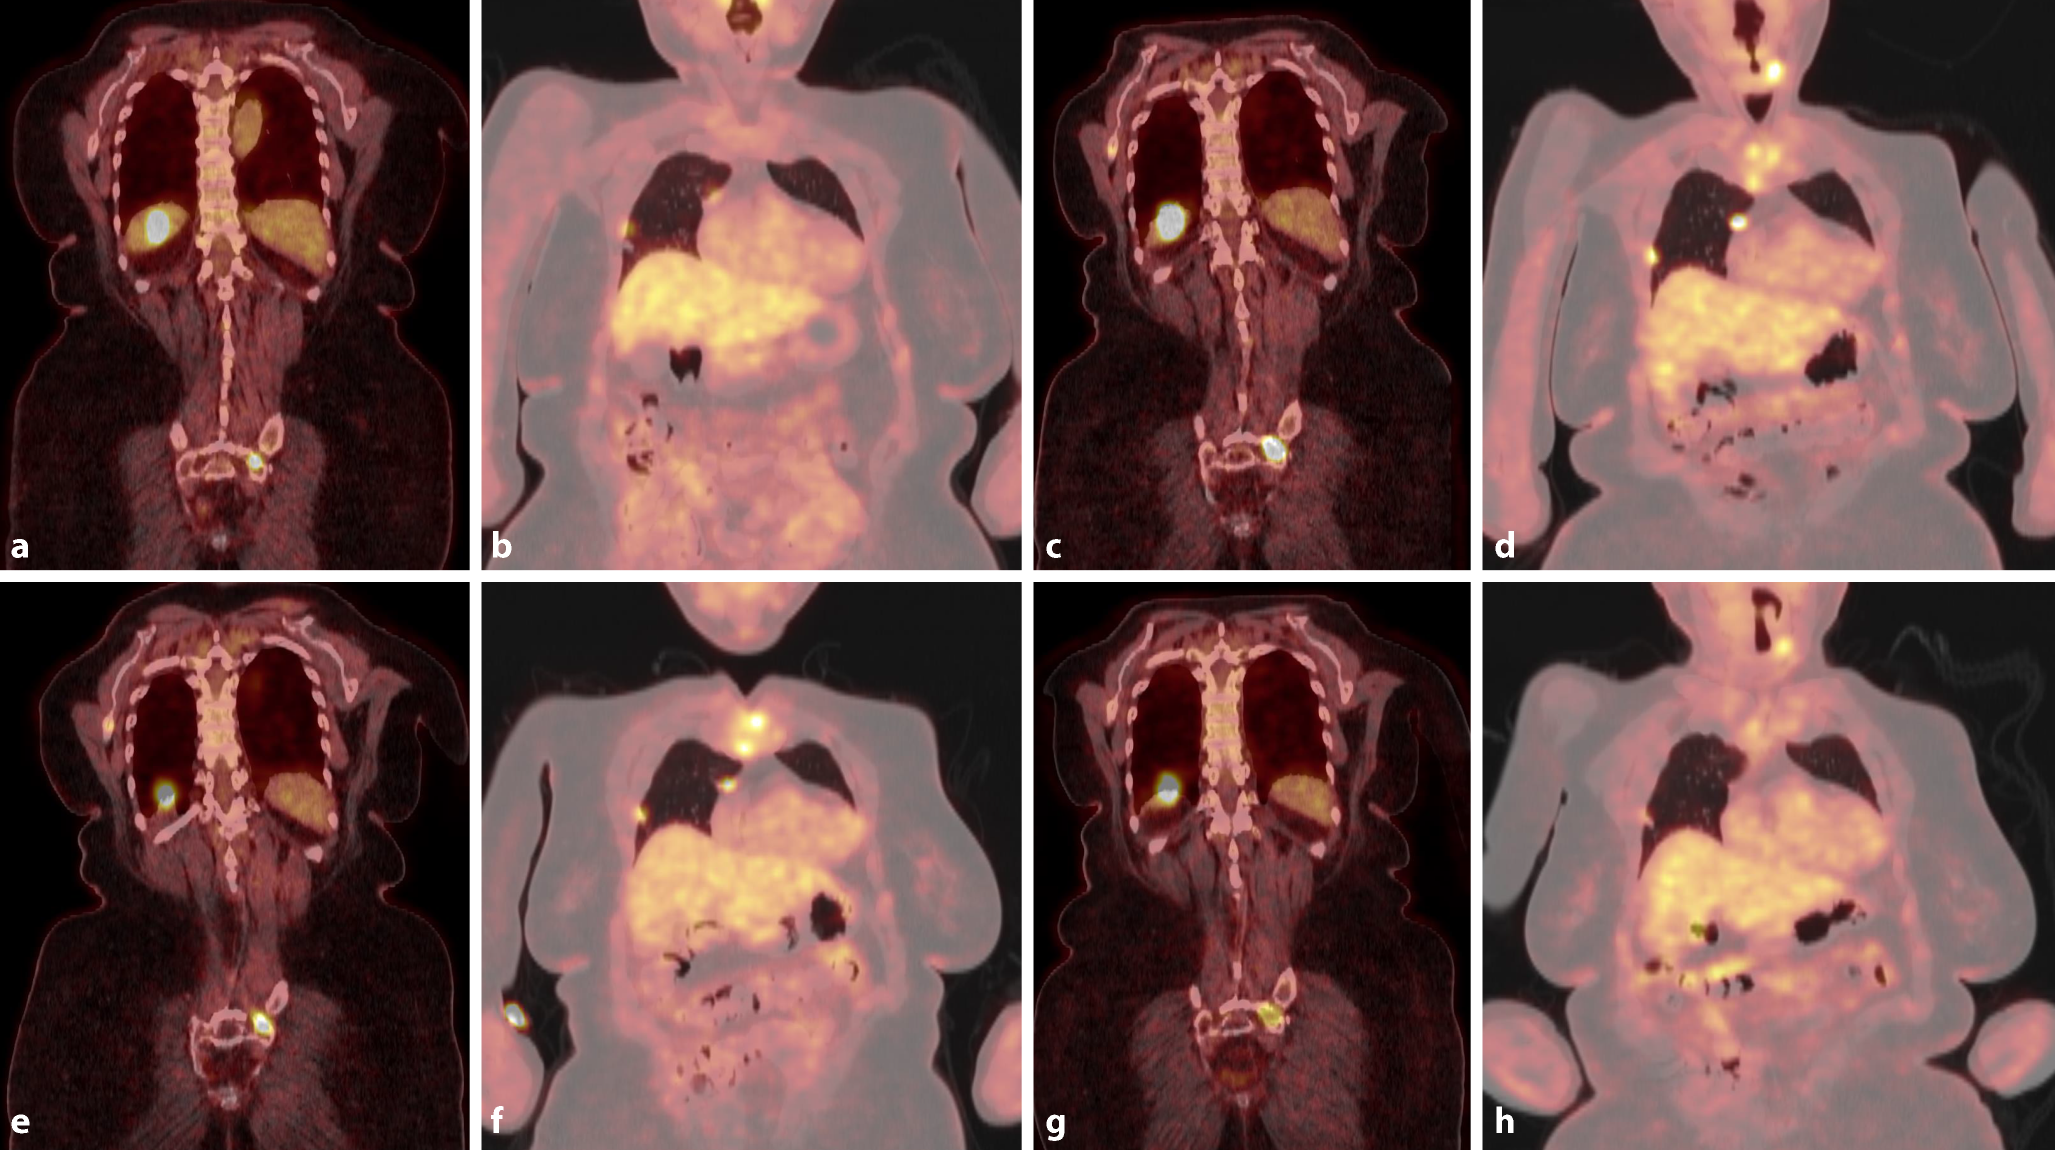

Ist dagegen das Befinden des Patienten durch tumorassoziierte Symptome eingeschränkt, sollte gerade bei fehlenden lokalen Behandlungsmöglichkeiten (Tab. 2) die Einleitung einer systemischen Therapie erwogen werden [1013]. Bei symptomatischen Patienten ist die Unterscheidung essenziell, ob es sich um ein tumorassoziiertes Symptom (Schmerzen durch ossäre Metastasen) handelt oder eine durch Komorbiditäten bedingte Reduktion des Allgemeinzustands vorliegt. Die pulmonale Metastasierung kann beim differenzierten Schilddrüsenkarzinom ausgeprägt, jedoch ausschließlich durch kleinherdige Metastasen gekennzeichnet sein. Bei rein pulmonaler und asymptomatischer Metastasierung erscheint erst ab Tumormanifestationen > 10 mm Durchmesser die Grundlage für die Einleitung einer TKI-Therapie gegeben zu sein [13]. Andererseits besteht eine inverse Beziehung zwischen metabolischem Tumorvolumen und Ansprechen auf eine Therapie mit TKI. Tumorassoziierte Symptome erfordern in jedem Fall eine rasche und gezielte Therapie. Der Fall einer 76-jährigen Patientin in Abb. 1 demonstriert die Möglichkeit, auch bei fortgeschrittener Tumorerkrankung in Abstimmung mit dem individuellen Patientenwunsch zu zufriedenstellenden Behandlungsergebnissen zu gelangen.

Abb. 1

76-jährige Patientin mit follikulärem, primär radiojodrefraktärem Schilddrüsenkarzinom. Bereits bei der Erstdiagnose 11/2018 rechtsseitig pulmonale, Leber- und Knochenmetastasen (a,b). Bei völliger Beschwerdefreiheit, Allgemeinbefinden ECOG 0, wurde dem dringenden Patientenwunsch entsprochen und die Umsetzung der Behandlungsempfehlung des Tumorboards zur Einleitung von Lenvatinib postponiert. Osteoprotektive Therapie mit Denosumab monatlich. c,d Die Bildgebung vom 25.02.2021 zeigt den langsamen, aber kontinuierlichen Progress in allen betroffenen Kompartments. Schließlich Einleitung der Systemtherapie mit Lenvatinib – Startdosis 24 mg tgl., Reduktion wegen starken Gewichtsverlusts, Diarrhö und Hand-Fuß-Syndrom auf eine Erhaltungsdosis von 10–14 mg tgl. alternierend (e,f nach 3‑monatiger Therapie). Der Tumormarker Tg fiel innerhalb von 3 Monaten nach Einleitung der Systemtherapie um 70 %. Seit 18 Monaten stabiler Befund mit Zeichen eines partiellen metabolischen Ansprechens ohne neue Tumormanifestation